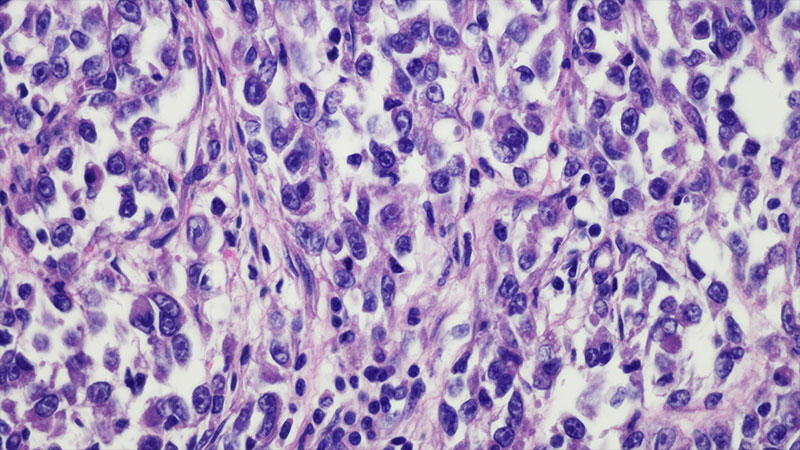

Clear cell sarcoma of the leg

The integrated Sarcoma Service for Cancers of the Bone and Soft Tissues at Columbia is a joint program among physicians in orthopedic oncology, hematology/oncology, and radiation oncology who collaborate on developing the optimal course of treatment for each patient. The therapeutic plan may involve surgery, chemotherapy, radiation and, at times, a combination of all three. Under the leadership of Wakenda K. Tyler, MD, MPH, Chief, Orthopedic Oncology Service, Columbia faculty are involved in gene analysis to identify specific genes that either produce a good response or a poor response to therapy, making it possible for our physicians to determine an alternate therapy with greater precision. Our orthopedic surgeons are also focused on the challenges of diagnosing intra-articular tumors, which are often mistaken for other non-neoplastic conditions, and the importance of recognizing when surgical or nonsurgical treatment is indicated.